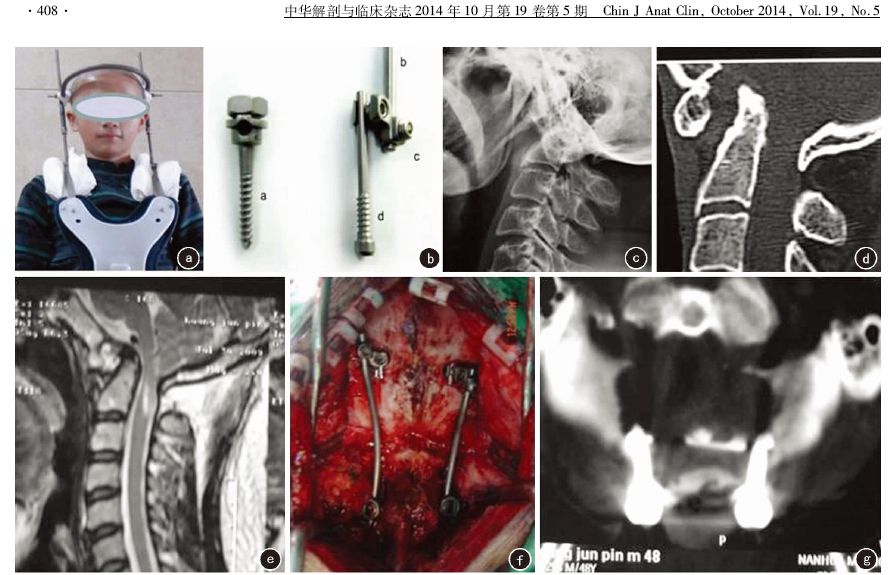

方法:回顾性分析2010年1月—2013年1月南华大学附属第一医院收治的15例颅颈部畸形患者资料,其中男9例,女6例,年龄29~60岁(40.4±8.2)岁。Arnold-Chiari畸形8例,寰枕融合并颅底扁平5例,颈椎分节不全( Klippel-Feil 综合征) 2例。术前CT 和MRI检查均提示寰枢椎脱位合并脊髓不同程度受压。术前日本矫形外科协会(JOA)评分为6~10分,平均(8.1±1.7)分。所有患者入院后均行颅骨持续牵引,均采用枕骨板障间螺钉固定系统进行枕颈融合术。

结果:手术均顺利完成,手术时间100~220 min(140.2±30.5) min;出血量190~710 ml(272.2±73.4) ml。无脊髓血管损伤及其他严重并发症。术后第3天JOA评分9~14 分,平均(11.0±2.1)分,较术前明显改善(t=0.003, P<0.05)。术后复查 X线片、CT和MRI提示板障间螺钉位置均满意,没有螺钉穿透枕骨内板。除1例复位不良外,余14例均完全复位,脊髓受压完全解除。随访12~36 个月,平均(22.0±6.3)个月,术后3~9个月(5.1±2.7)个月植骨均获得骨性融合,无断钉、断棒及内固定松动发生。末次随访时JOA评分为12~16分,平均(14.1±1.6)分。与术前比较明显改善,差异有统计学意义(t=0.002, P<0.05)。

结论:颅骨持续牵引结合枕骨板障间螺钉固定系统进行枕颈融合术具有固定牢靠、操作简单、方便植骨等优点,是治疗颅颈部畸形的有效方法。